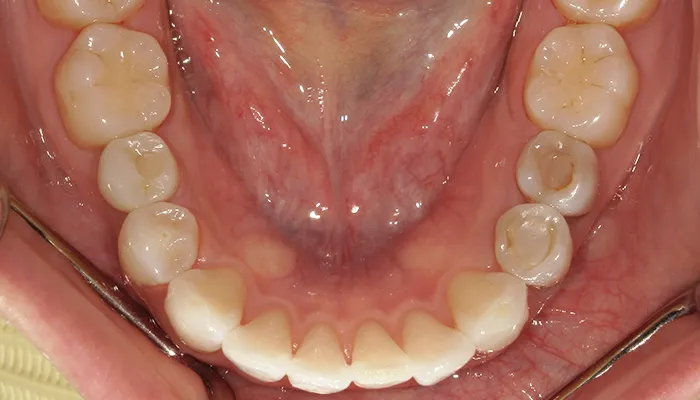

治療後の口腔内写真

術後の口腔内写真

右下5番のインプラントは良好に骨結合し、自然な形態と色調の補綴物を装着しました。

インビザライン矯正により歯列が整い、清掃性・咬合バランスともに改善しました。

ホワイトニングにより歯全体の色調が明るくなり、笑顔の印象が大きく改善しました。

患者様は審美性・機能性ともに大変満足していらっしゃいました。